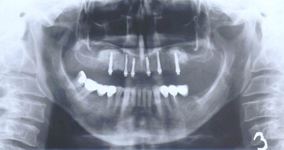

Tento výkon se nazývá sinus lift - aplikace kostního granulátu do čelistní dutiny

Při ztrátě molárů a premolárů v horní čelisti a jejich náhradě implantáty se často setkáváme s nedostatečnou

vertikální nabídkou kosti pod čelistní dutinou, často doprovázenou i nedostatečnou horizontální nabídkou a sníženou kvalitou kosti (v oblasti 2. premoláru v 50%, v oblasti moláru až v 80% případů nedostatečná kostní nabídka)

Od roku 1985 je tento problém řešen augmentační operací nazývanou

sinus lift.

Jedná se o vyzvednutí membrány, která čelistní dutinu vystýlá, pod vyzvednutou membránou vznikne kapsa, kam se umístí augmentační materiál, do kterého se zavedou implantáty.

Vhojení implantátů se při této operaci prodlužuje na 6-12 měsíců.